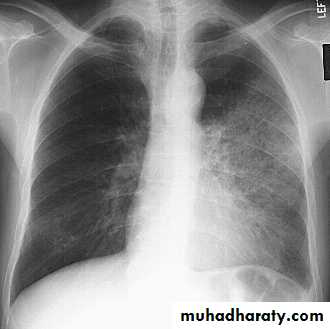

blunting of the costophrenic angle

blunting of the cardiophrenic angle

fluid within the horizontal or oblique fissures

eventually a meniscus will be seen, on frontal films seen laterally and gently sloping medially

with large volume effusions, mediastinal shift occurs away from the effusion

Obliteration of costo-pherinic anglesMeniscus sign

Lenticular sign